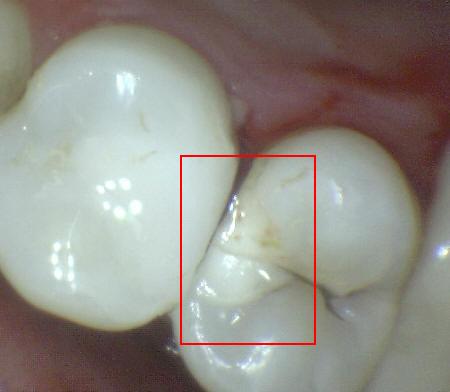

Código 3

(Caries Moderada): Ruptura

localizada del esmalte debido a caries sin dentina visible.

-

La superficie seca muestra una perdida detectable de la

estructura del esmalte. El diente visto en estado

húmedo pueden tener una clara opacidad de caries (mancha blanca

/ marrón)

Una

sonda paeriodontal puede deslizarse sobre la

lesión para comprobar micro-cavidad (pérdida de la

integridad de la superficie de esmalte < 0,5 mm.)